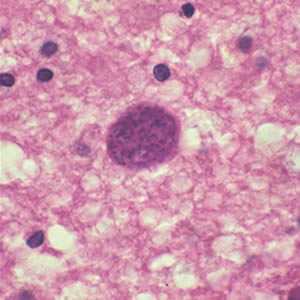

Toxoplasma gondii cyst in brain tissue.

Figure A: Toxoplasma gondii cyst in brain tissue stained with hematoxylin and eosin.

Figure B: Toxoplasma gondii cyst stained with hematoxylin and eosin.